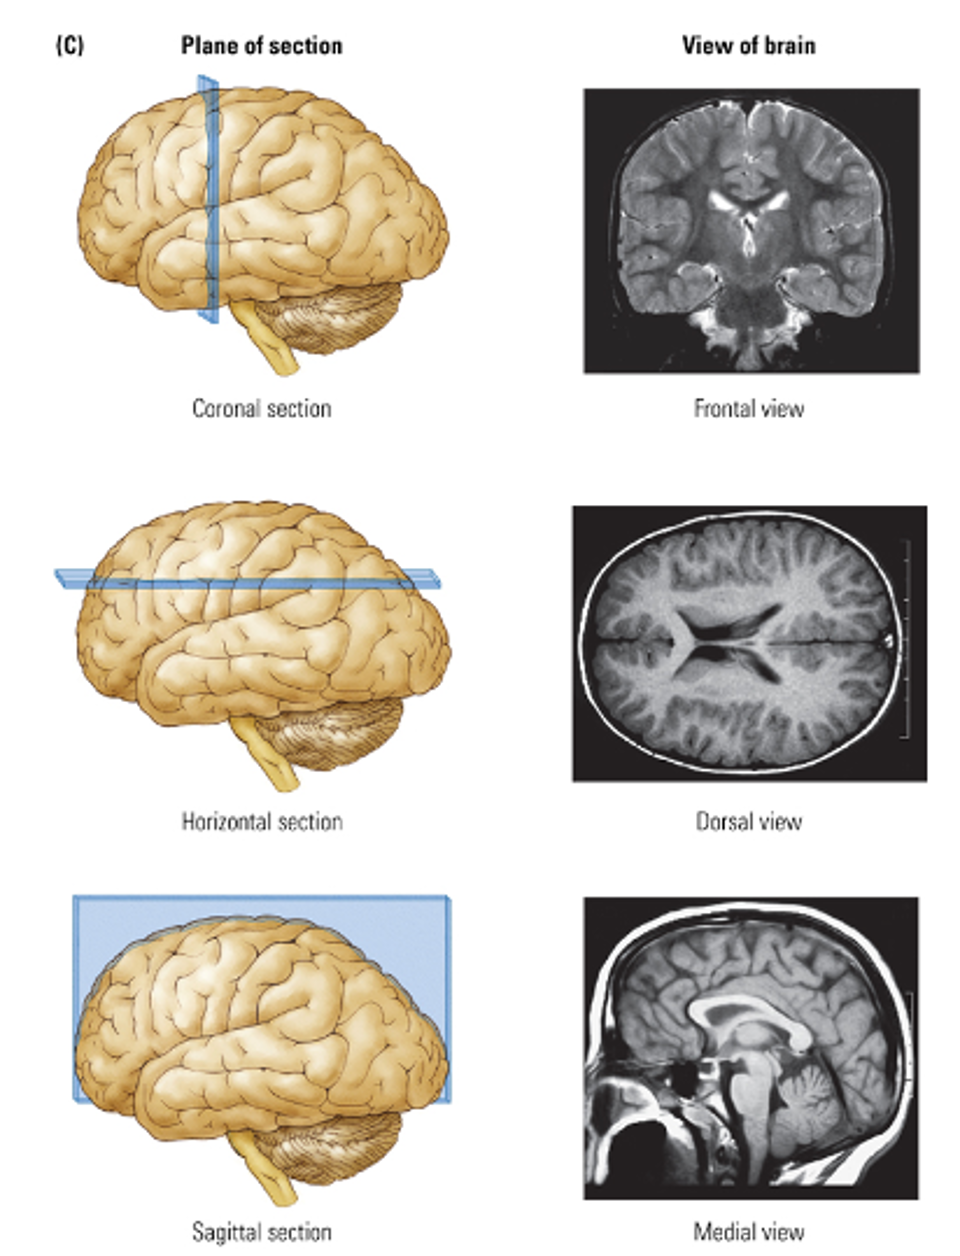

What are the planes of the brain?

Coronal section → Frontal view

Horizontal section → Dorsal view

Sagital section → Medial view (clear access to hypothalamus pituitary)